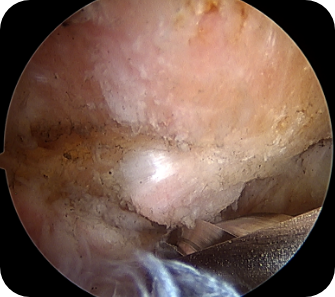

회전근개 질환, 오십견, 어깨 탈구 등 어깨 질환은 어깨의 통증과 고통을 야기합니다. 어깨 관절내시경 수술은 관절 질환이 의심되는 부위를 1cm 미만으로 최소절개한 뒤, 내시경 카메라와 수술 기구를 관절 내부에 삽입해 질환을 진단하고 치료하는 수술입니다. 화면을 통해 병변 부위를 직접 확인할 수 있어 손상 정도에 따라 파열된 힘줄을 봉합하거나 염증을 제거할 수 있습니다. CT나 MRI 등의 진단으로 잘 보이지 않던 곳까지 내시경을 삽입할 수 있어 적용 범위가 점점 넓어지고 있는 추세입니다.